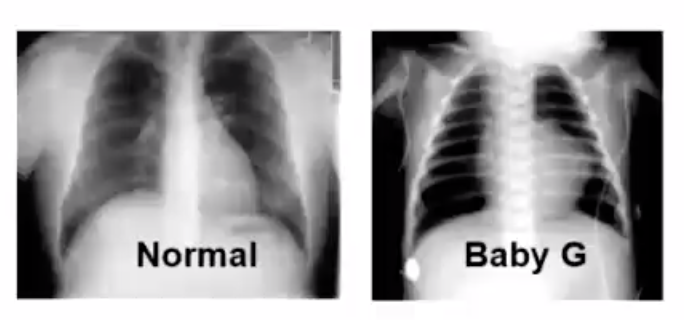

Baby G was born at term and seemed healthy the first few days. On the 4th day, the baby turned progressively cyanotic. Oxygen administration did not improve her colour. On chest x-ray, lungs looked dark. A harsh murmur was heard to the left of the upper sternum. What is occuring?